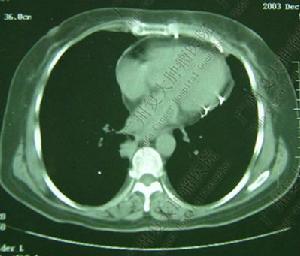

3.CT檢查可提示部分腫瘤的部位和性質

如心包囊腫:①2/3位於右前心膈角,位於在膈肌上;②典型的淚滴狀”伏在心包旁,邊緣光滑銳利。③囊壁薄,大部份含純清液體。CT值0-20HU。又如心包間皮瘤:①心包不規則增厚,前緣可見類結節樣組織肺物。②心包內大量積液,並雙側胸腔積液,右冠狀動脈鈣化(圖52-11)。